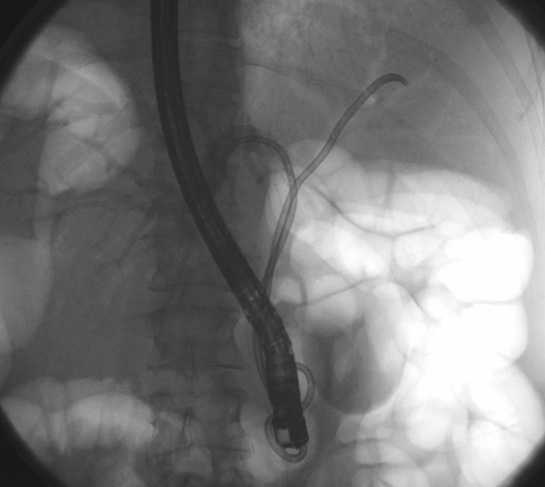

Histopatolojik sınıflama, tümörlerin malignite potansiyelini belirlemede kritik bir rol oynamaktadır. Evrelendirme (Staging) Evrelendirme, tümörün vücutta ne kadar yayıldığını belirlemek için kullanılan bir sistemdir. En yaygın evrelendirme sistemi, TNM sistemidir ve üç ana unsurdan oluşur: